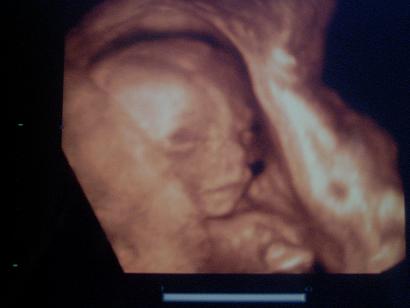

Úgy szerettem, amikor mocorogtak. Habár Gréti olyan kis finoman mozgott, hogy néha már azt mondtam, hogy megyek a védőnőkhöz, hallgassák meg a szívhangját, hogy él-e még ez a gyerek

De aztán mindig rúgott 1-2-t, hogy megnyugodjon az anyja